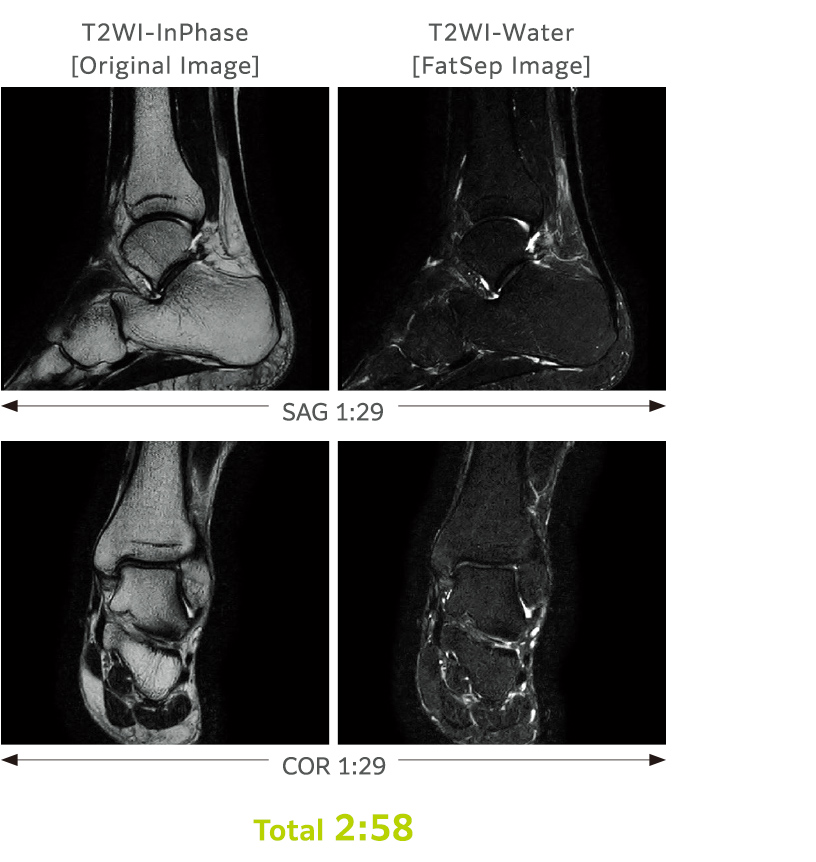

FatSep bir tür baskılama yöntemidir ve manyetik duyarlılıktaki değişikliklerden daha az etkilenir.

Rezonans frekansındaki fark (su protonları ve yağ protonlarının kimyasal kaymaları) kullanılarak tek bir taramayla birden fazla görüntü elde edilebilir.